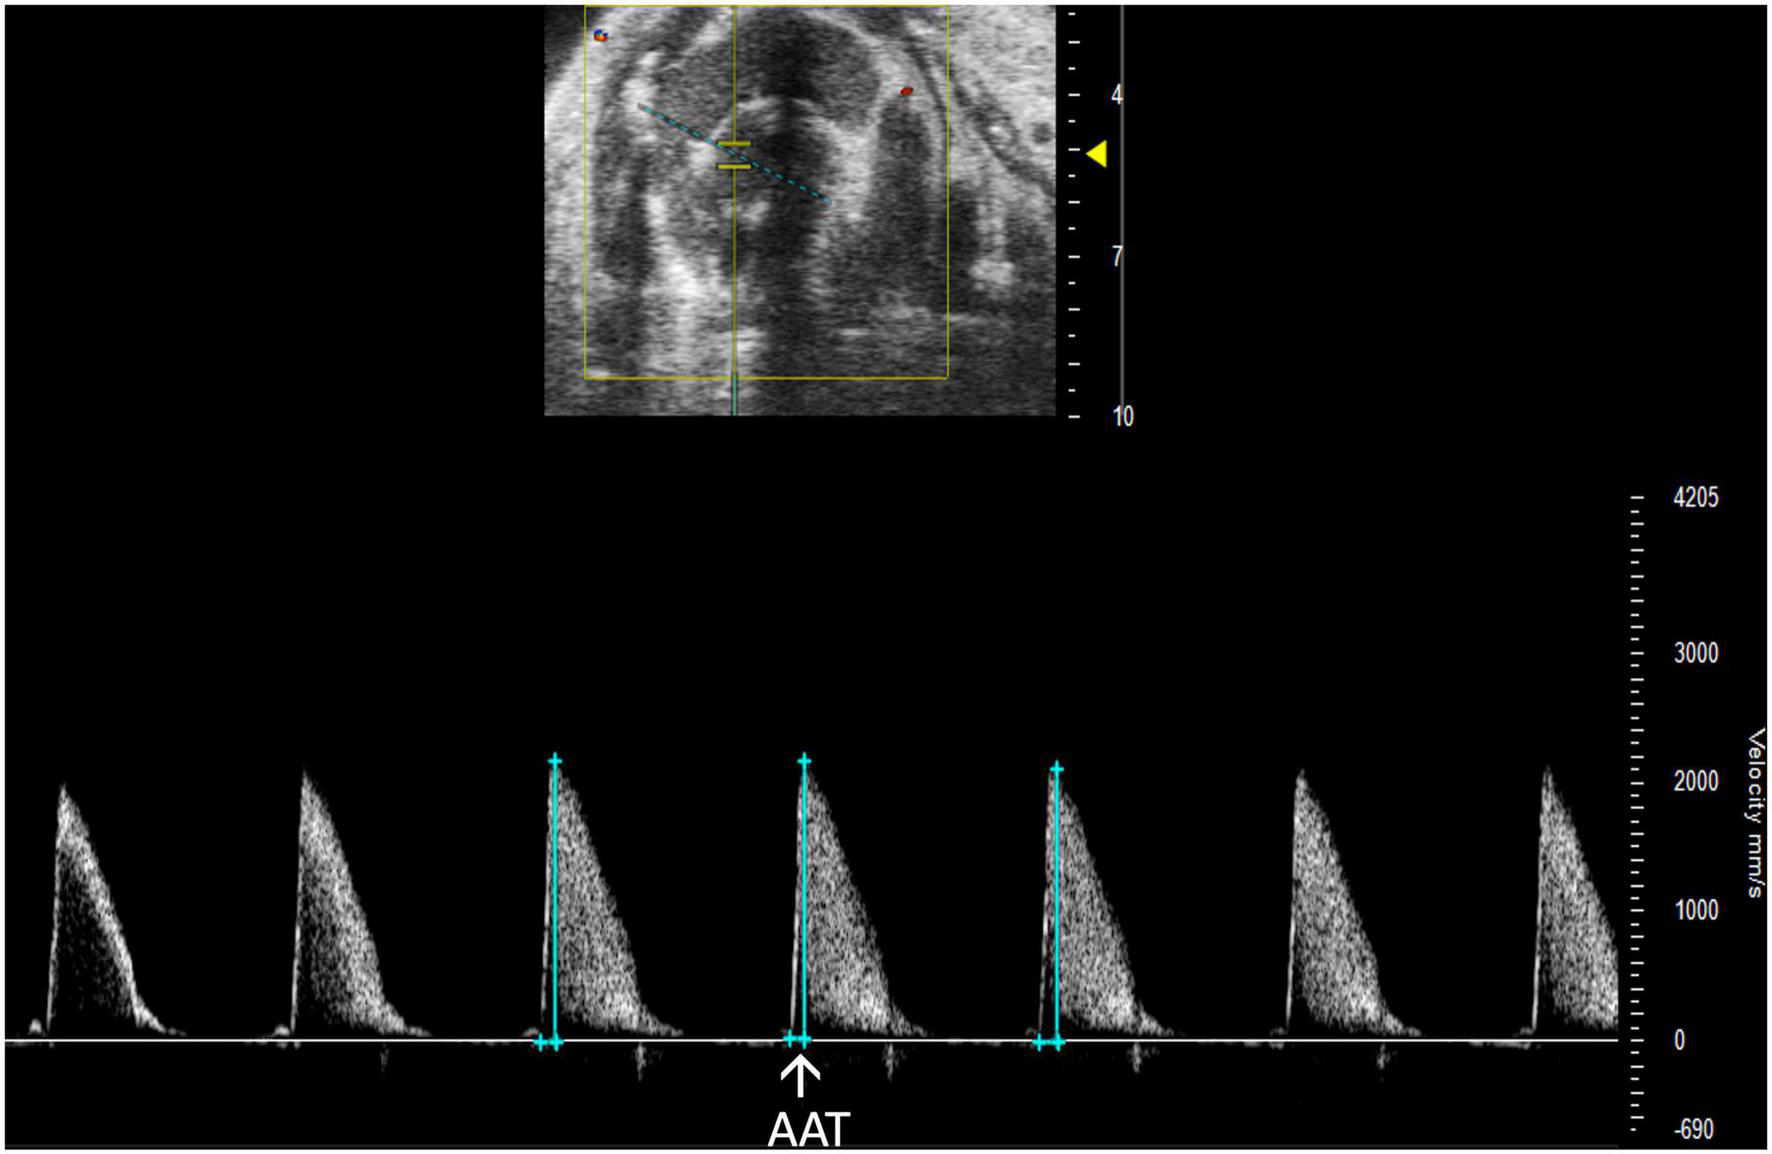

2.3.4.2 Aortic acceleration time

Aortic acceleration time (AAT) has been validated by Perez et al. to assess LV contractility in mice. It is measured in PW Doppler mode as the time to peak aortic velocity (Figure 14). Studies in humans suggest that the ratio of AAT to aortic ejection time (AET) predicts aortic stenosis severity (14), although it has not yet been evaluated in mice.

FIGURE 14

Pulsed wave (PW) Doppler mode image showing analysis of the aortic acceleration time (AAT), a measurement of left ventricular contractility in mice.